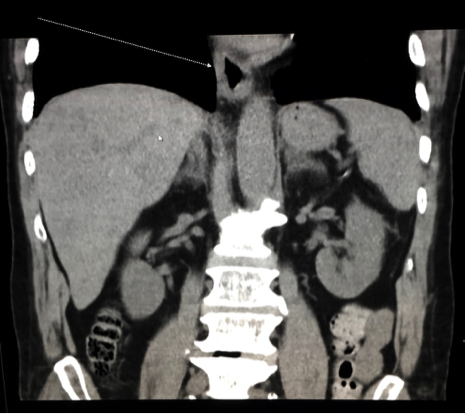

Abdominal ultrasonography scans showed mild diffuse fatty infiltration of the liver. Computed tomography (CT) scans of the abdomen showed mild circumferential mural thickening of the lower esophagus (Figures 1 and 2).

Figure 2. Abdominal CT, coronal view, showing circumferential mural thickening of the lower esophagus.